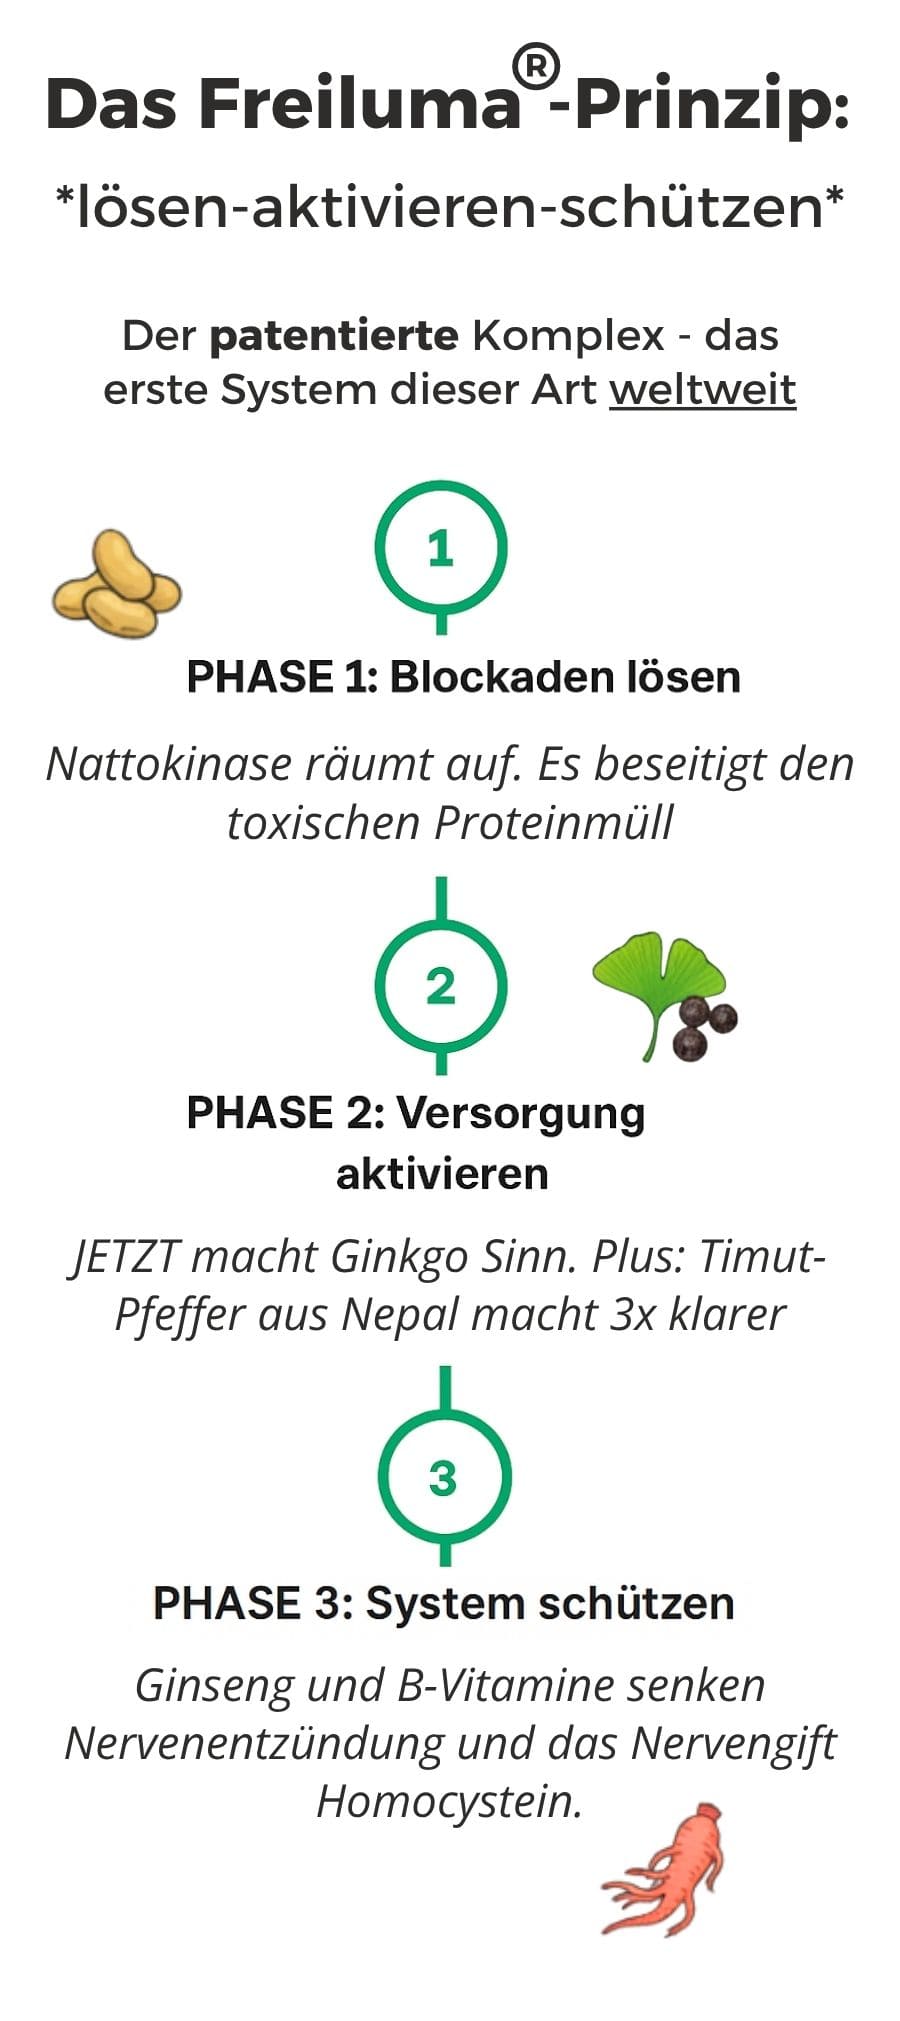

Das Freiluma®-Prinzip: Die deutsche Innovation

Während Japan Nattokinase konsumiert und Nepal den Timut-Pfeffer nutzt, blieb es deutschen Forschern vorbehalten, beides zu kombinieren.

Der patentierte Freiluma™-Komplex - das erste 3-Phasen-System weltweit:

Die einzige Kombination in Deutschland mit Nattokinase in Pharmaqualität, Ginkgo (NACH Blockadenlösung), Timut-Pfeffer (Nepals Geheimnis) sowie Ginseng + B-Komplex (Langzeitschutz)

- Nattokinase (Pharmaqualität)

- Ginkgo (Pharmaqualität)

- Timut-Pfeffer (Pharmaqualität)

- Ginseng (Pharmaqualität)